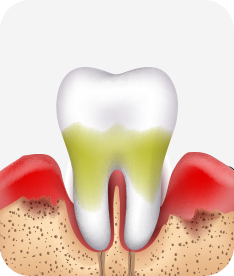

치주염(잇몸병)은 치아에 붙어있는 치석 및 세균 등에 의한 염증반응으로 잇몸뼈가 상실되는 질환을 말합니다.

초기에는 잇몸이 붓거나 잇몸에서 피가 나는 증상이 나타나며 계속 방치하면 치아를 발치해야 할 수도 있습니다.

치주염 단계별 증상

치주염 (중기~말기)

주기적으로 잇몸이 붓고 피가 나며, 욱씬하거나 우리한 통증이 나타남.

치주치료 및 정도에 따라 치주수술(잇몸수술)이 필요함. 향후 관리 정도에 따라 3~6개월 간격으로 내원하여 유지치료를 시행하여야 함.